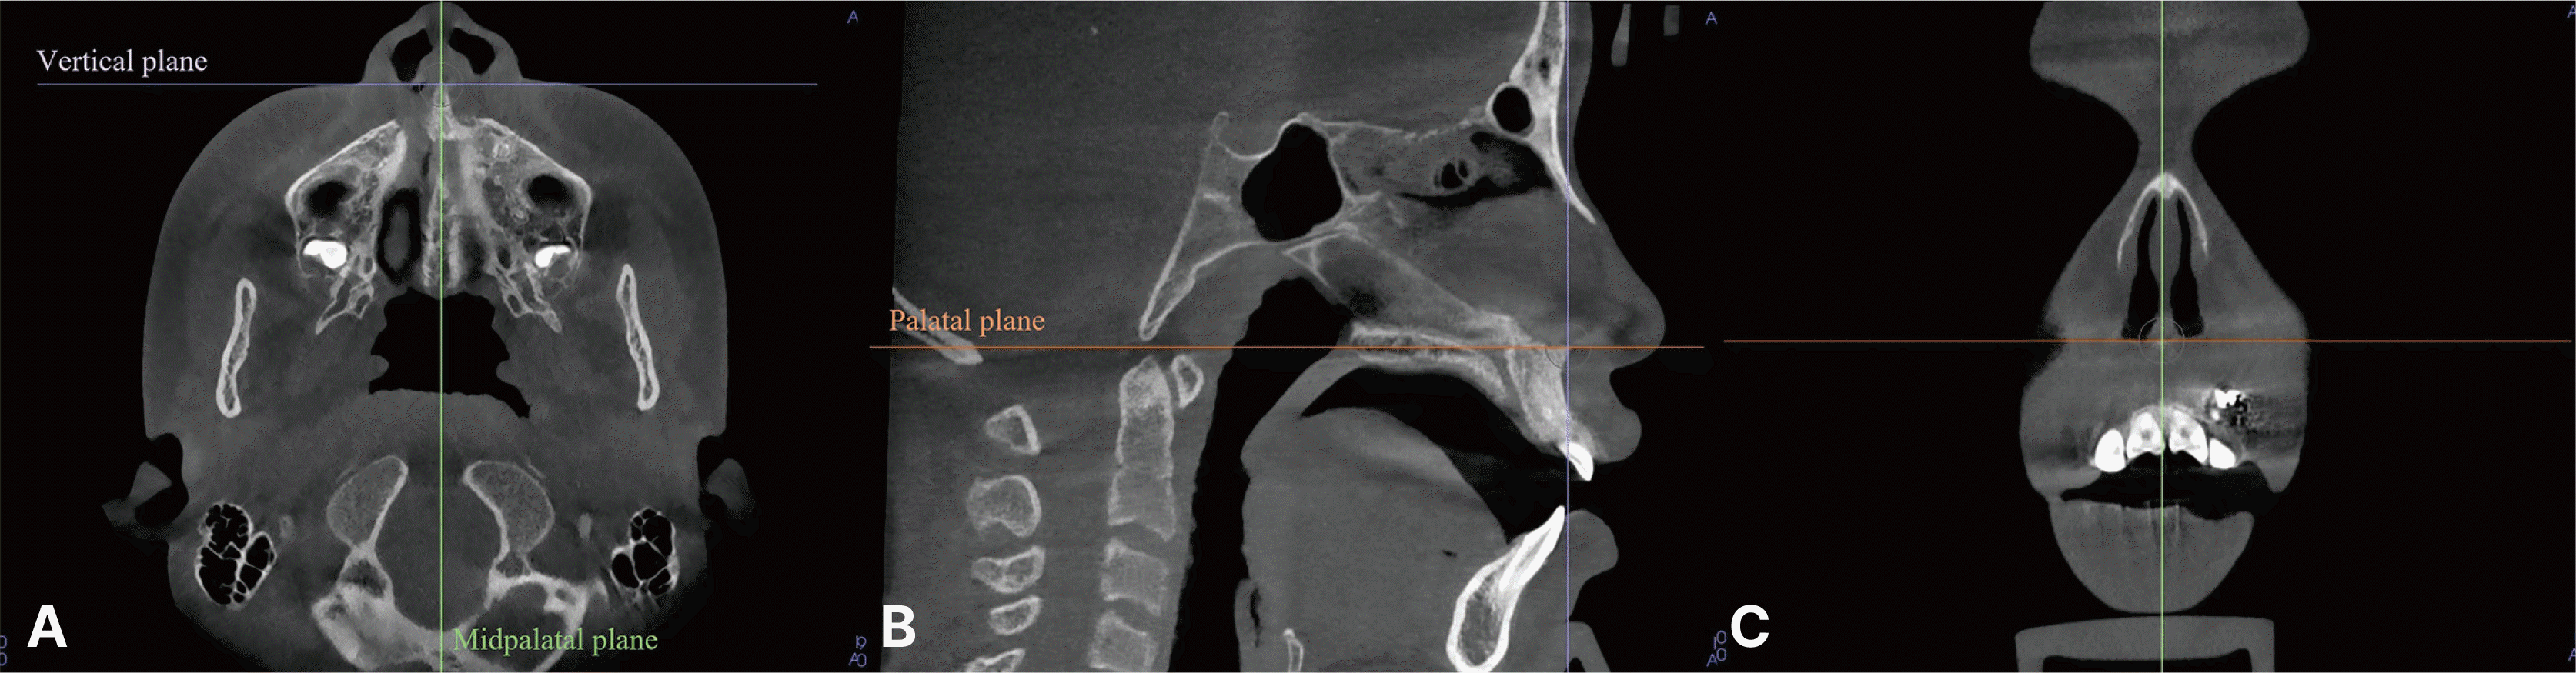

The CBCT images in this study were analyzed using Invivo 6 plus, version 6.5 software (Anatomage, San Jose, USA) by a single investigator (J.E.J). Variables such as rotation, angulation, torque, root volumes, root lengths, and the presence of hooked apices were measured. The palatal plane, defined by the horizontal line connecting both orbitales and passing through the ANS and PNS, served as the horizontal reference. The midpalatal plane, passing through the ANS and PNS and perpendicular to the palatal plane, was used as the vertical reference. A vertical plane through the ANS and perpendicular to both the palatal and midpalatal planes functioned as the transversal reference (Fig. 1).